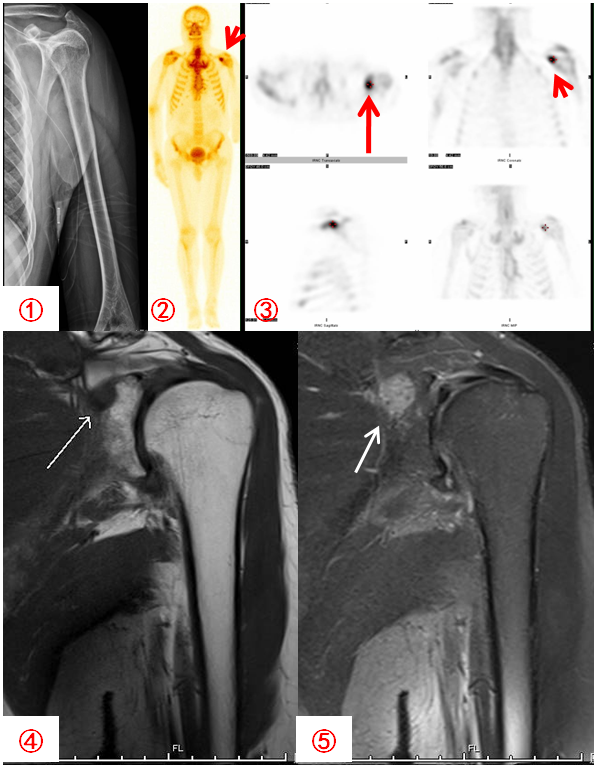

胃癌患者,自述左上臂痛,DR拍片未見明顯異常(圖1);骨顯像示左肩關節異常濃聚(圖2,紅箭),SPECT斷層顯像定位于左肩胛骨(圖3,紅箭);MR顯示病灶與ECT所示一致(圖4、5白箭)。